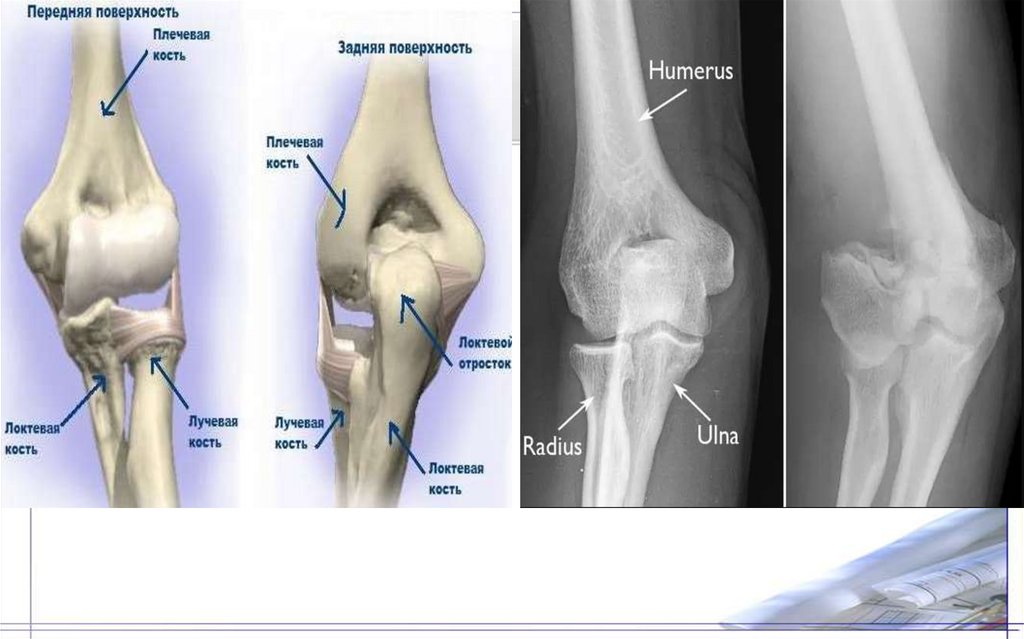

36. Плечевая кость(Humtrus)